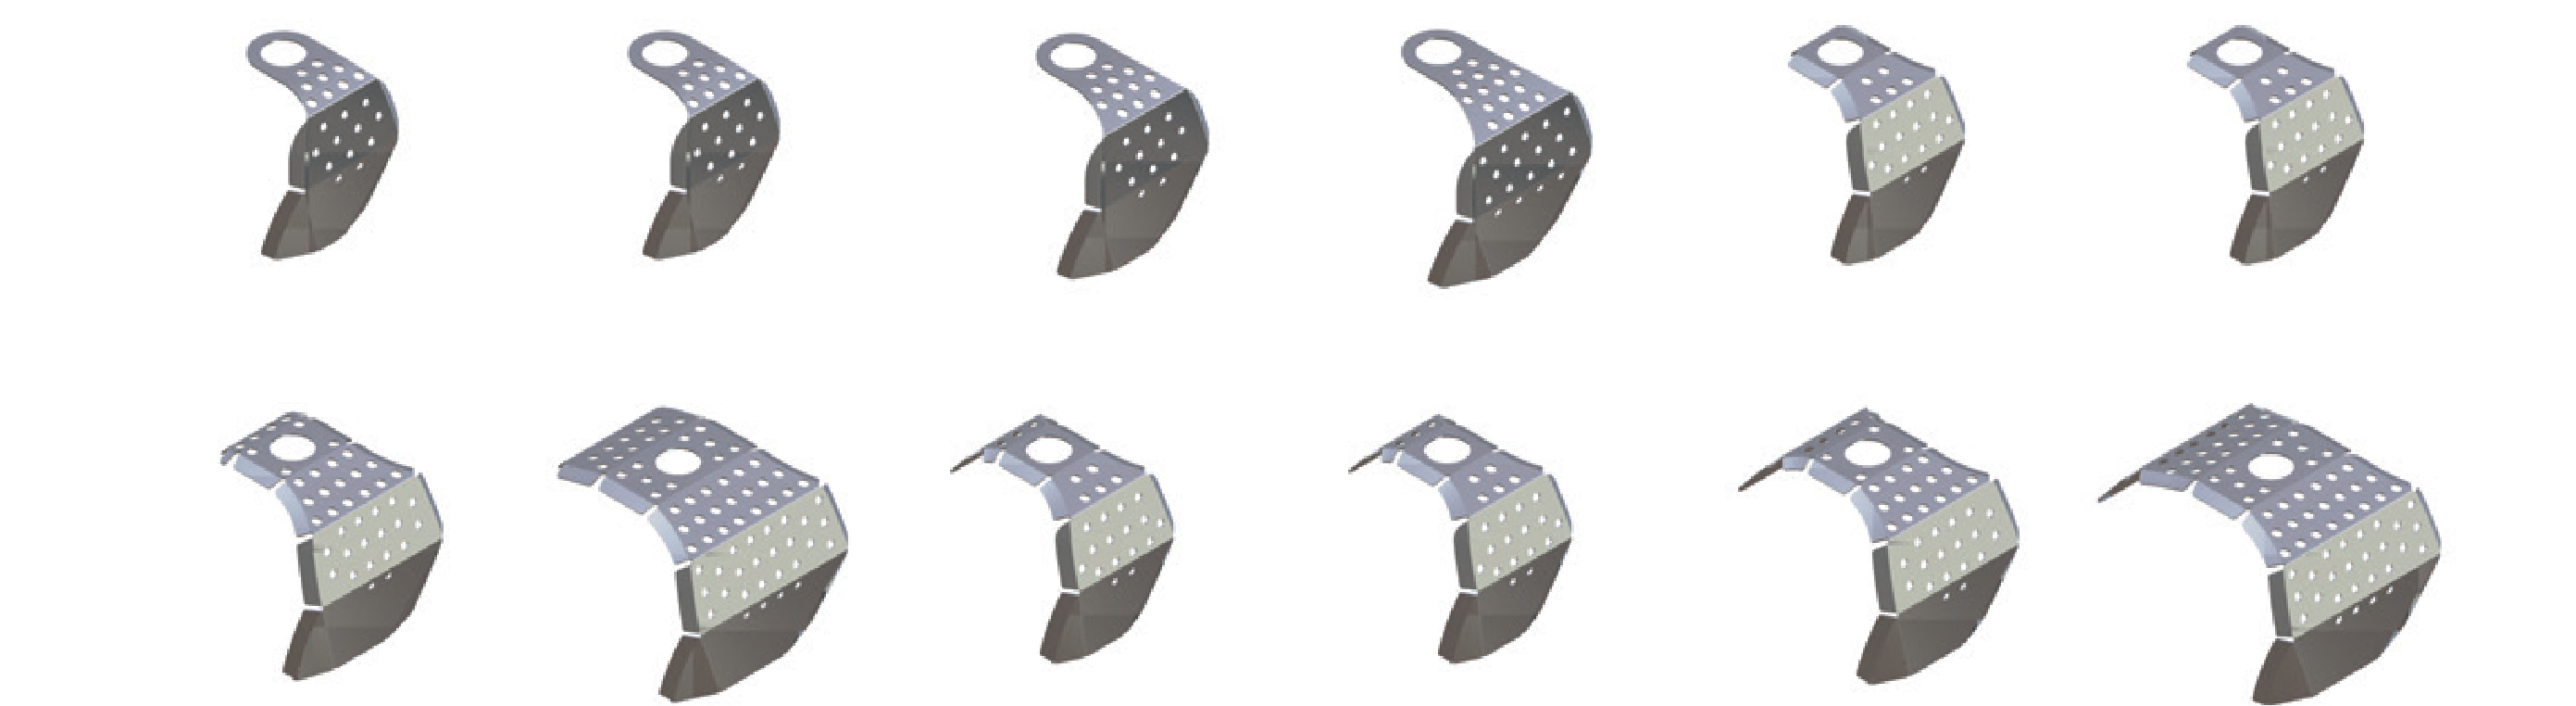

Pre-Shaped Design

To avoid the inconvenience of modeling titanium membrane in the clinic, i-Gen has 12 pre-formed sizes in varying shapes.